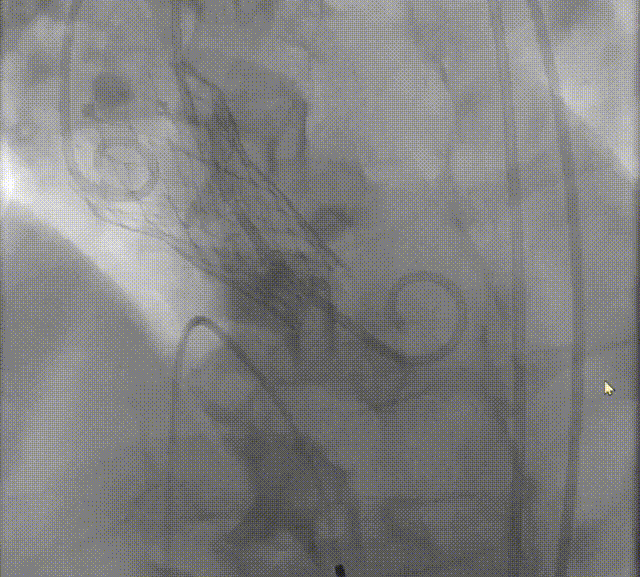

23mm Z-Med后扩张

最终结果

在评判植入深度是否合理时,应特别关注瓣架形态,特别是瓣架底部扩张形态。如底部呈现“收口”形态,应谨慎评估植入深度,必要时回收瓣膜,调整为更深的释放位点;

当瓣膜完全释放后,瓣架仍呈“收口”形态,应充分评估后扩风险与获益,决定是否要后扩;

如需后扩,球囊充盈时建议轻推球囊,且待完全回抽球囊后再停起搏 ,以降低瓣膜脱位风险。